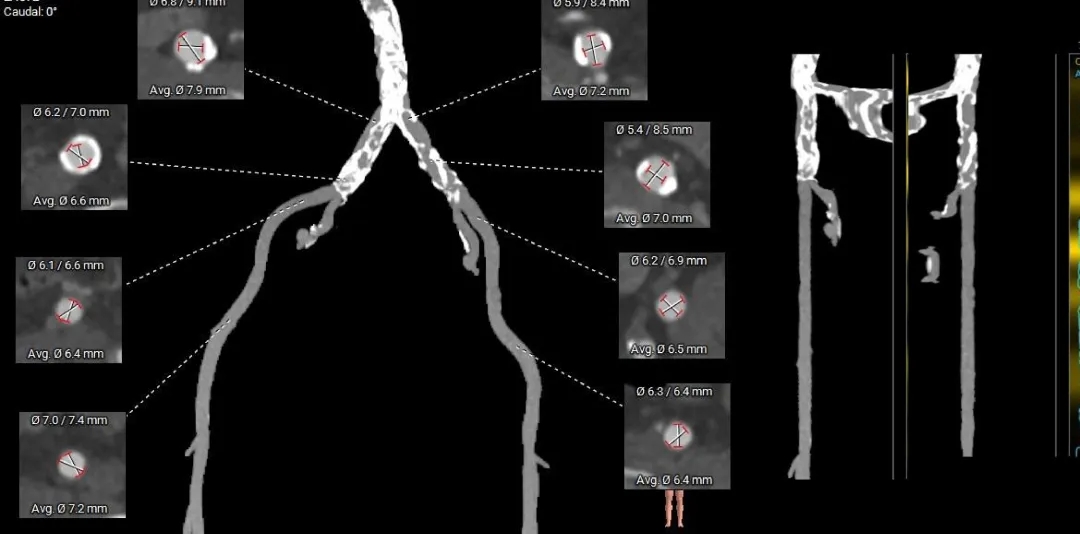

术前CT分析

TYPE-1L-R融合二叶瓣,中-重度钙化,流出道收口型,升主动脉未见扩张;

双侧冠脉高度可,冠脉阻挡风险不高;

瓣环水平夹角75°,横位心;

外周血管内径充足,双侧髂动脉及腹主动脉可见明显钙化,无明显迂曲;

根据瓣环及瓣上结构选择 ScienCrown TF25mm瓣膜。

主动脉根部测量

Annulus

22.8mm

LVOT

20.4mm

钙化积分:

665mm3

SOV:

33.1*35*34.3mm

STJ:

34.5mm

AAO:

41.2mm

瓣上结构测量

瓣上2mm

23.6mm

瓣上4mm

23.8mm

瓣上6mm

22.5mm

瓣上8mm

冠脉风险评估

外周入路评估